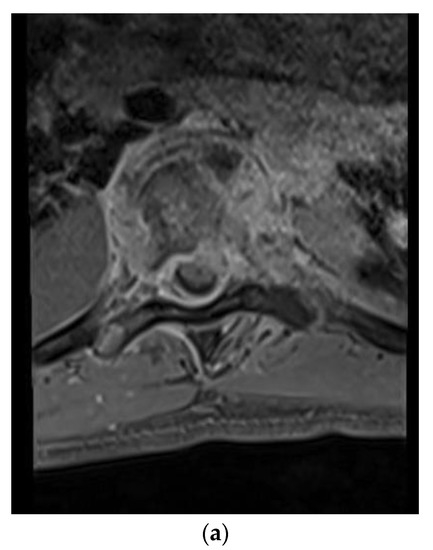

A 54-year-old man with a past medical history of hypertension, C3–4 osteomyelitis, prevertebral/epidural abscess, and left septic knee who presented initially to his primary care physician with left upper extremity and lower extremity weakness, left knee pain, and lab results remarkable for elevated white blood cell count. Infectious disease workup and joint aspiration of the left sternoclavicular joint infection with coccidioidomycosis were confirmed. He was treated with intravenous fluconazole and vancomycin. The MRI and CT scan for evaluating the weakness revealed osteomyelitis/discitis of C3–4 and a focal epidural abscess (Figure 3a,b). In addition, he was diagnosed with a left septic knee and underwent aspiration of joint effusion. A repeat MRI of the cervical spine later revealed improvement in the size and inflammation of the epidural abscess, and the patient was discharged on IV liposomal amphotericin B 50 mg per day. A few weeks later, the patient presented to the emergency room with fever, tachycardia, and tingling in the bilateral upper extremities. MRI of the cervical spine revealed retrolisthesis of C3 and C4, spinal canal stenosis, and cord compression due to extension of the epidural abscess into the level of the C5 vertebra. Furthermore, extensive discitis and osteomyelitis with collection in both the epidural and prevertebral regions were noted. The patient was clinically noted to have motor weakness in the left upper extremity and was transferred to our institution for a higher level of care and management. The abscess was surgically treated with incision and drainage of the prevertebral abscess, a C4 corpectomy, C3–5 fusion with placement of a cage, and an anterior plate from C3–5. Figure 3a shows the Coccidiodes spherules in the ventral epidural abscess. During the hospitalization, he also underwent several debridement procedures and arthrocentesis of his infected left knee.

Figure 3. (a) Sagittal T1-weighted MR images with contrast showing extensive disc space destruction at C3-4 with epidural enhancement. (b) Sagittal cervical spine CT showing postoperative erosion of the C4 vertebral body significant retrolisthesis of C3 onto C4. (c) H&E stain of the cervical spinal pathologic specimen demonstrating the Coccidioides spherules within soft tissue, which is morphologically compatible with coccidioidomycotic osteomyelitis.